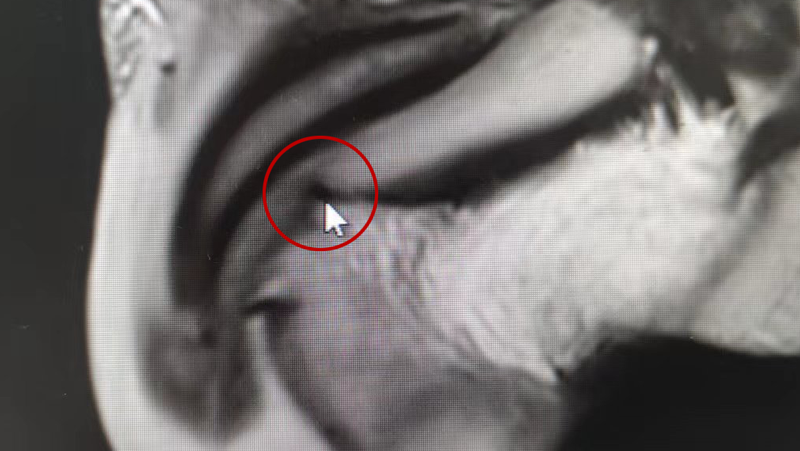

通過(guò)陰囊及附睪MRI平掃

考慮“丁丁”海綿體部

局部挫傷并周?chē)[形成

從圖中可看到

陰莖由兩根海綿體組成

內(nèi)有豐富的血管竇

外面被堅(jiān)韌的白膜所包繞

白膜是封閉陰莖海綿體的

一層膜狀組織